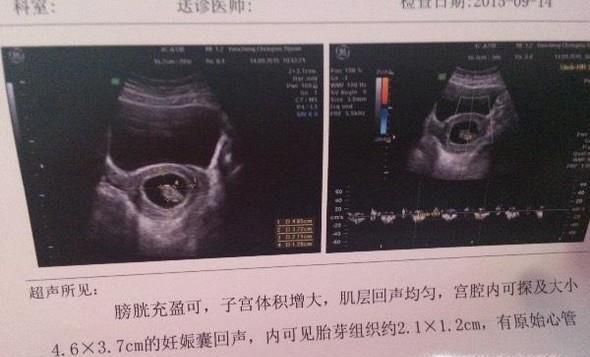

操作方法01、B超,虽然医生不会直接告诉大人孩子的性别,不过B超中的胎儿形状会有一定鉴别性。